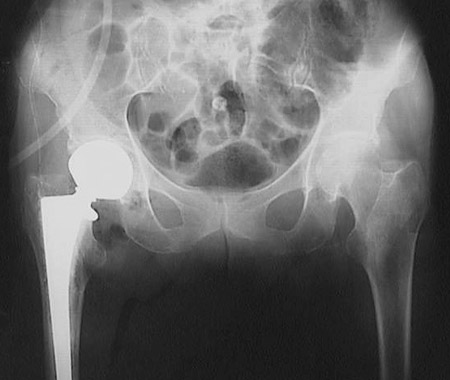

The radiograph of the pelvic region shown above reveals a prosthesis for the hip joint necessitated by a femoral fracture in an older person with osteoporosis.